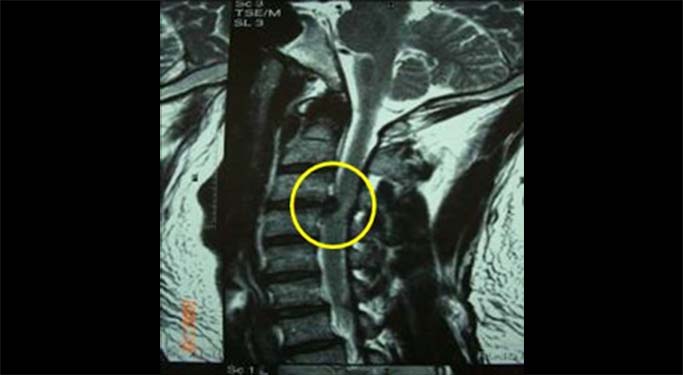

頚椎椎間板ヘルニアのMRI画像